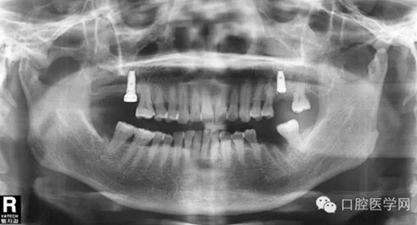

第五種,瑞士士卓曼種植體(也稱ITI種植體)